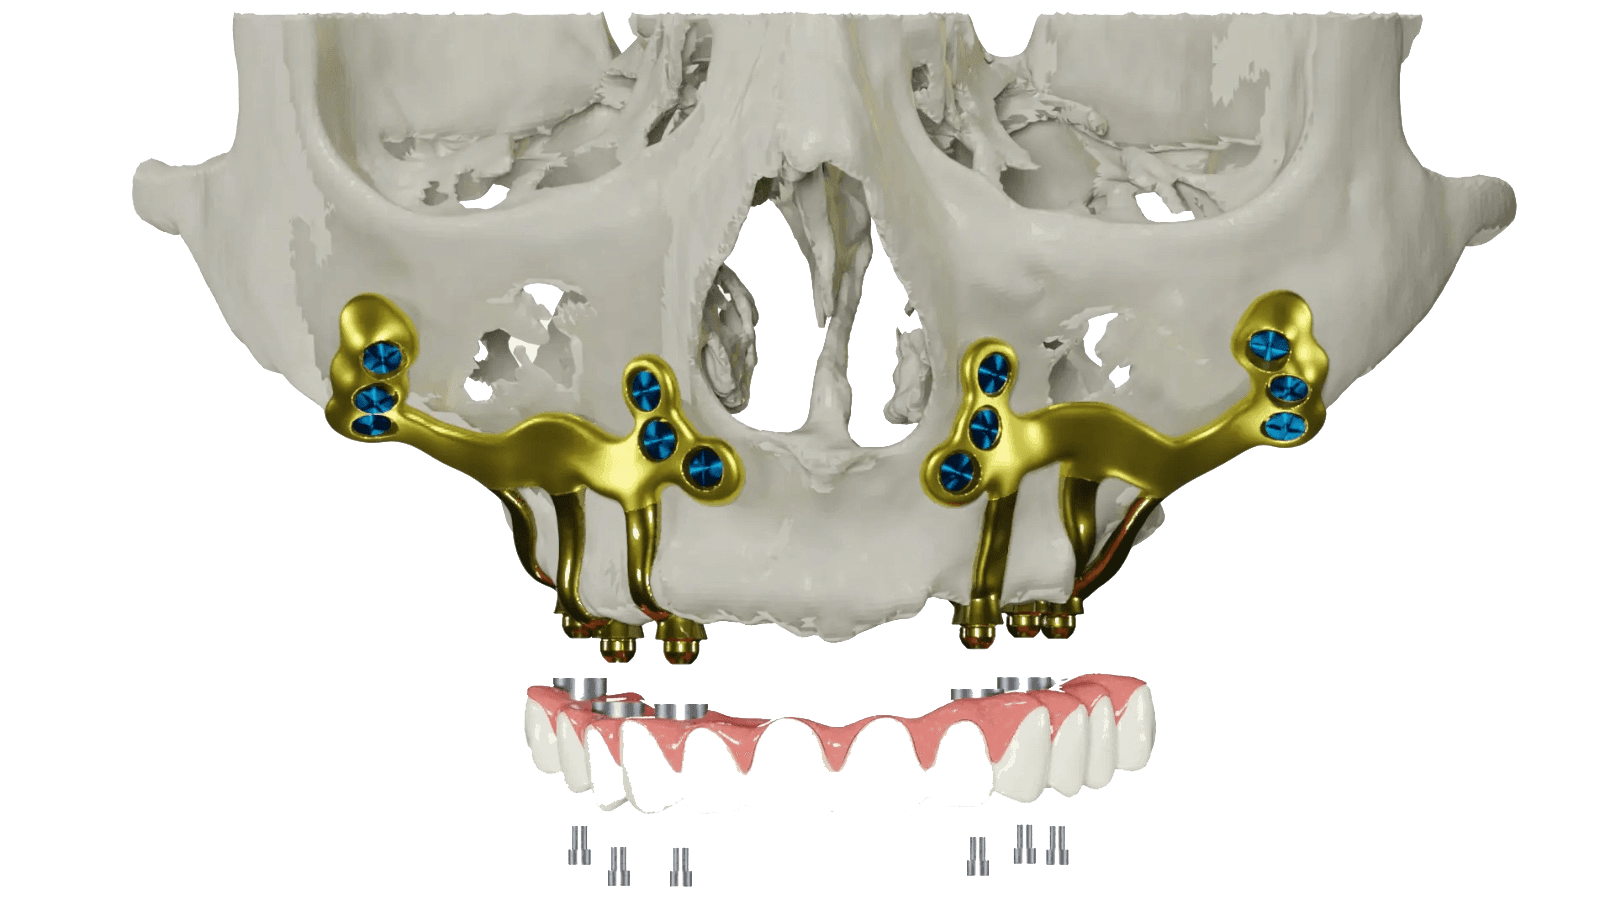

Subperiostale Implantate werden auf der Oberfläche des Kieferknochens, unter dem Zahnfleischgewebe, eingesetzt und können sowohl im Ober- als auch im Unterkiefer verwendet werden. Da sie keine Knochentransplantation erfordern, bieten diese individuell angefertigten Implantatstrukturen selbst bei minimal vorhandenem Knochen eine stabile und zuverlässige Grundlage für festsitzenden Zahnersatz.

Subperiostal Implantate sind eines der Verfahren, die bei Patienten mit partiellem oder totalem Zahnverlust (Zahnlosigkeit) angewendet werden, unter Bedingungen, bei denen das Knochenvolumen nicht durch Knochenaugmentationsverfahren (Knochenaufbau) vergrößert werden kann, oder wenn Knochenaugmentationsverfahren von den Patienten nicht bevorzugt werden. Es handelt sich um individuell angefertigte Implantate. Im Gegensatz zu konventionellen Implantaten ist es kein System, das in den Knochen eingesetzt wird, sondern ein Implantatsystem, das auf der Knochenoberfläche und unter dem Weichgewebe, das die Knochenoberfläche umgibt/bedeckt und als Periost (Knochenhaut) bezeichnet wird, platziert wird.

Diese Methode bietet Patienten dank einer speziell auf dem Knochen (unter dem Periost) platzierten Titanrahmenstruktur die Möglichkeit einer festsitzenden Prothese in kurzer Zeit. Auf diese Weise können Zahnimplantatbehandlungen bei Patienten durchgeführt werden, die aus Gründen wie Parodontalerkrankungen oder Traumata einen schweren Knochenverlust erlitten haben.